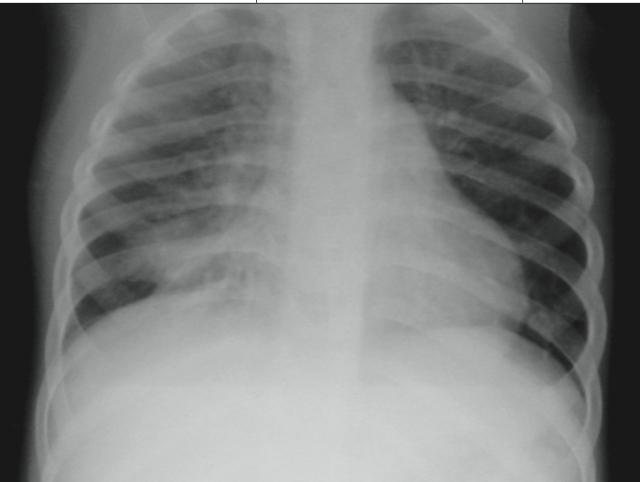

Typically, chronic cough is a lingering manifestation of a viral upper respiratory tract infection; other, more serious causes—such as asthma, upper airway disorders, or gastroesophageal reflux—must also be...